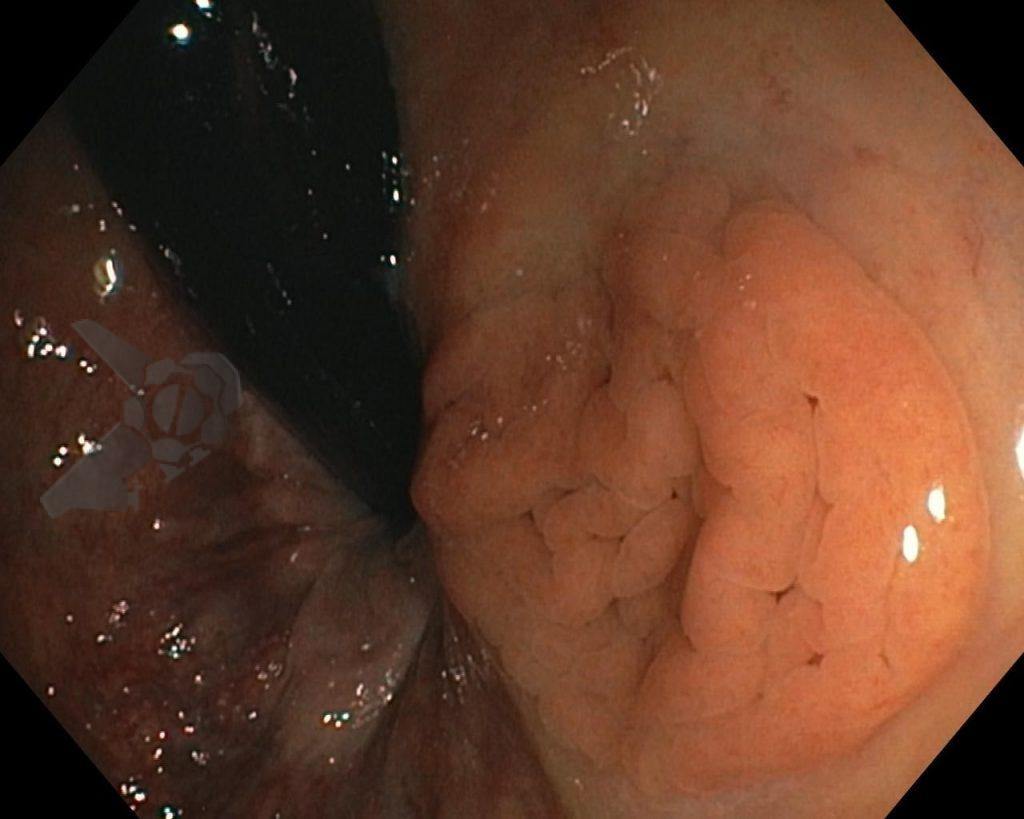

Paciente do sexo feminino, 54 anos, hipertensa, com relato de um episódio de hematoquezia ocorrido há 30 dias. Nega perda ponderal ou alteração do hábito intestinal. Realizou colonoscopia, sendo identificada, em reto distal, próximo à linha pectínea, lesão mostrada abaixo medindo cerca de 2 cm.

Foi realizada cromoscopia com índigo carmim e biópsias.